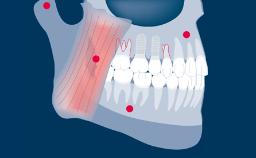

Prosthodontic Planning and Procedures

Design Principles for Combining Single Unsplinted Dental Implants and Partial Removable Dental Prostheses (RDPs)

Learning Module